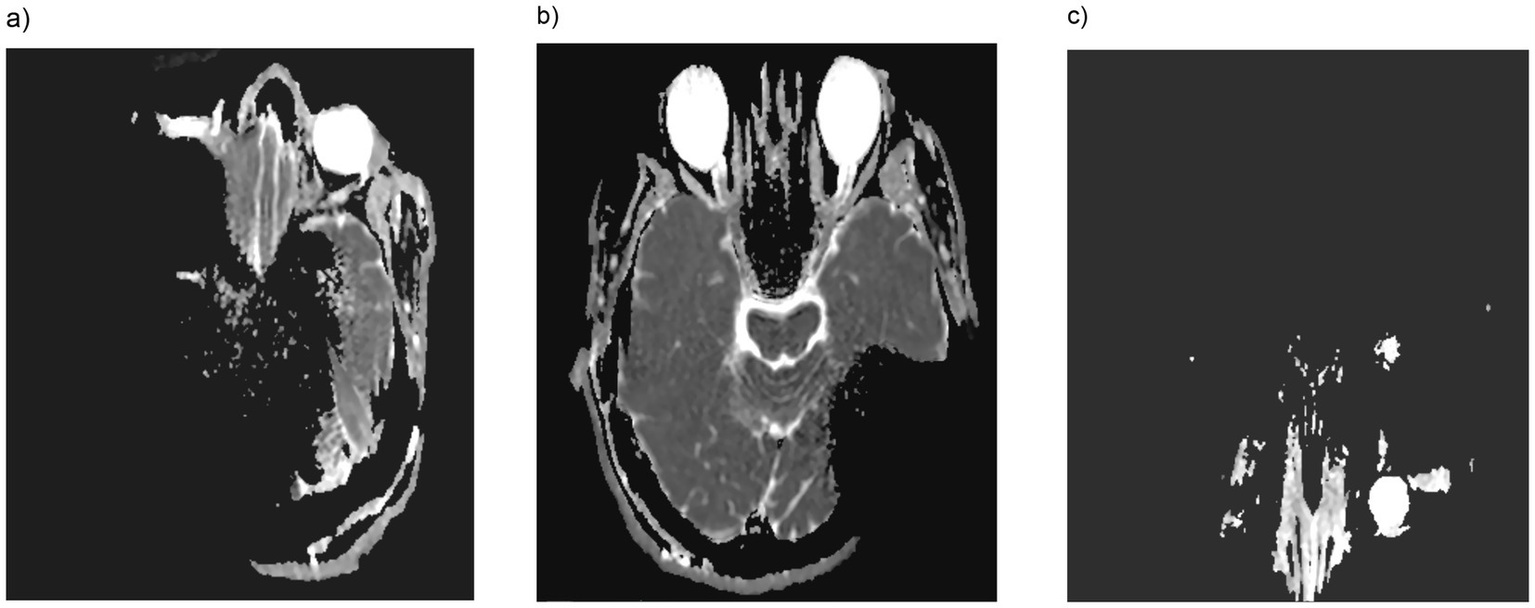

The orbit was visible and assessable under the examined conditions for T1, T2 and TIRM sequences (see Figure 1), even in bilaterally implanted patients with the magnet in situ (Table 2). The eyeball, as well as the straight and oblique extraocular muscles, the optic nerve, the medial bony boundary to the ethmoid bone (lamina papyracea), the lateral boundary, the orbital floor, were clearly visible and assessable in the T1 and TIRM sequences. However, in some sequences, particularly T1, the orbital roof was not fully assessable, leading to a downgrade in visibility to category 2. Nevertheless, in DWI (diffusion weighted imaging) the orbit was not clearly assessable ipsi- and contralaterally especially in 90° and 120° positioned CI and in bilateral CI condition with magnet in situ, while in 135° positioned CI without magnet the orbit was accessible (see Figure 2).

Figure 1

MRI (magnetic resonance imaging) in T2-weighted sequence (a) and T1-weighted turbo inversion recovery magnitude (TIRM) images (b) in a unilateral CI with a magnet positioned at a 120° angle. As shown, both the contralateral and ipsilateral orbits are fully visible and assessable.

Figure 2

In DWI (diffusion weighted imaging) orbital accessibility for 135° cochlear implant positioning was impeded with the magnet in place unilaterally (a) or bilaterally (c), whereas without the magnet (b), the orbit was clearly visible and accessible.